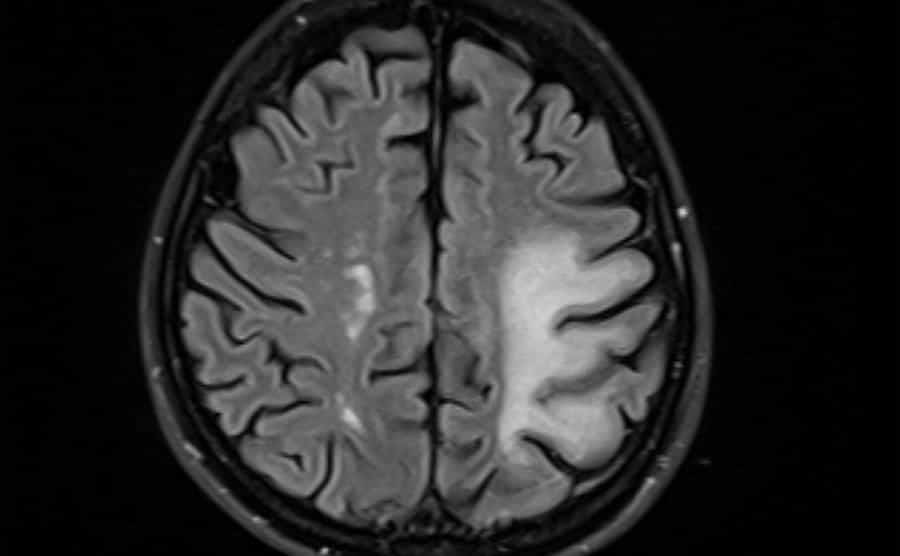

For example, when she had her neurologist appointment to get her brain scan results, Greg forgot to take the day off of work so that he could go with her. When she went to that appointment, she found out that she had damage to her right frontal lobe.

Damage to Her Frontal Lobe

The frontal lobe is an area in the brain that controls nonverbal abilities, such as memory. The neurologist explained that he was almost certain it came as a result of the lightning strike. Apparently, Greg never even asked Shana how it went, so she never told him.